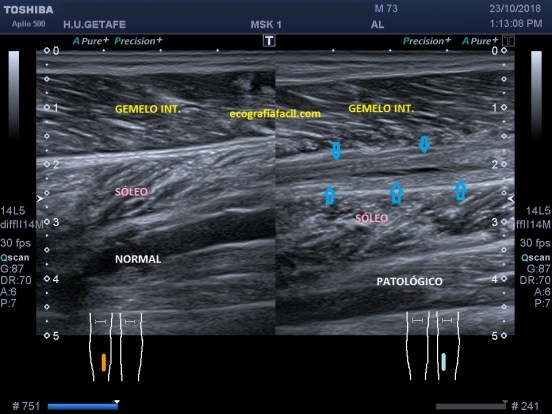

Compara la imagen 1 y la 2, grábala en tu memoria fotográfica. Ambas son unas imágenes en corte longitudinal del teste derecho de dos pacientes distintos.